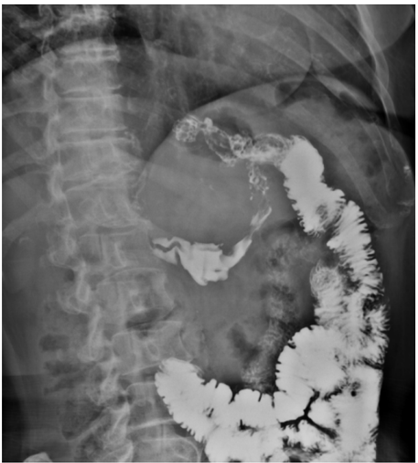

Mulher de 55 anos, submetida à cirurgia bariátrica há 6 meses sob técnica de bypass gástrico em Y de Roux, queixa-se de desconforto epigástrico e de dores intermitentes no abdome superior há 3 meses, sendo solicitado pelo médico cirurgião exame contrastado do esôfago-estômago-duodeno, representado pelas duas imagens abaixo. Obs.: contraste administrado por via oral.

Diante do exposto acima, analise as afirmativas abaixo e assinale a alternativa correta.

I. Há refluxo de contraste da via alimentar para a via biliopancreática por incompetência da anastomose terminolateral jejuno-jejunal.

II. Os achados evidenciam a presença de fístula entre a anastomose bolsa gástrica-alça jejunal e o estômago excluído.

III. Observa-se extravasamento de meio de contraste para a cavidade abdominal, achado suspeito para deiscência da anastomose bolsa gástrica-alça jejunal.